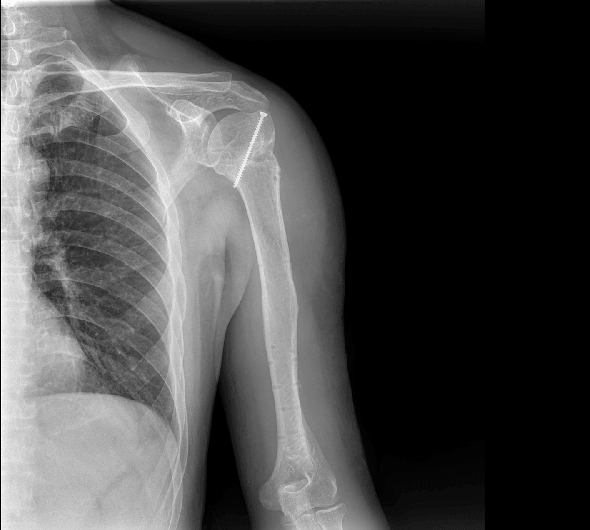

臨床圖像